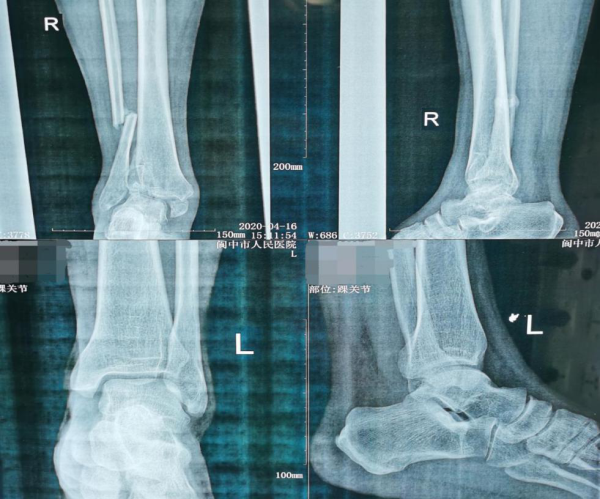

患者为一中年男子,因5个月前外伤后右踝肿痛、畸形,因受伤时,正值疫情期间,害怕到医院来“感染病毒”。便一直在找的“游医”给予了所谓的“外敷中药”等一系列治疗,但花费了大量的时间以及费用后,右踝关节仍反复肿痛。近期还出现了畸形加重,不能负重行走等症状。无奈之下只能到我院求诊。我院骨科接诊后,足踝组宋小飞组长仔细研究了患者的病情,他认为患者病情较重、受伤时间较长、部分骨折已畸形愈合、踝关节半脱位明显,且患者对保踝治疗要求较高。经过医患双方反复沟通,最终达成一致,进行手术治疗。

该手术由骨科宋晓飞与龙俊任两位医生共同完成,历时2小时,顺利完成了关节清理、截骨矫形、植骨等一系列手术,恢复了后足力线和踝关节稳定性,术中外观恢复正常,患者和家属对治疗结果非常满意,目前患者正在积极的康复治疗中。